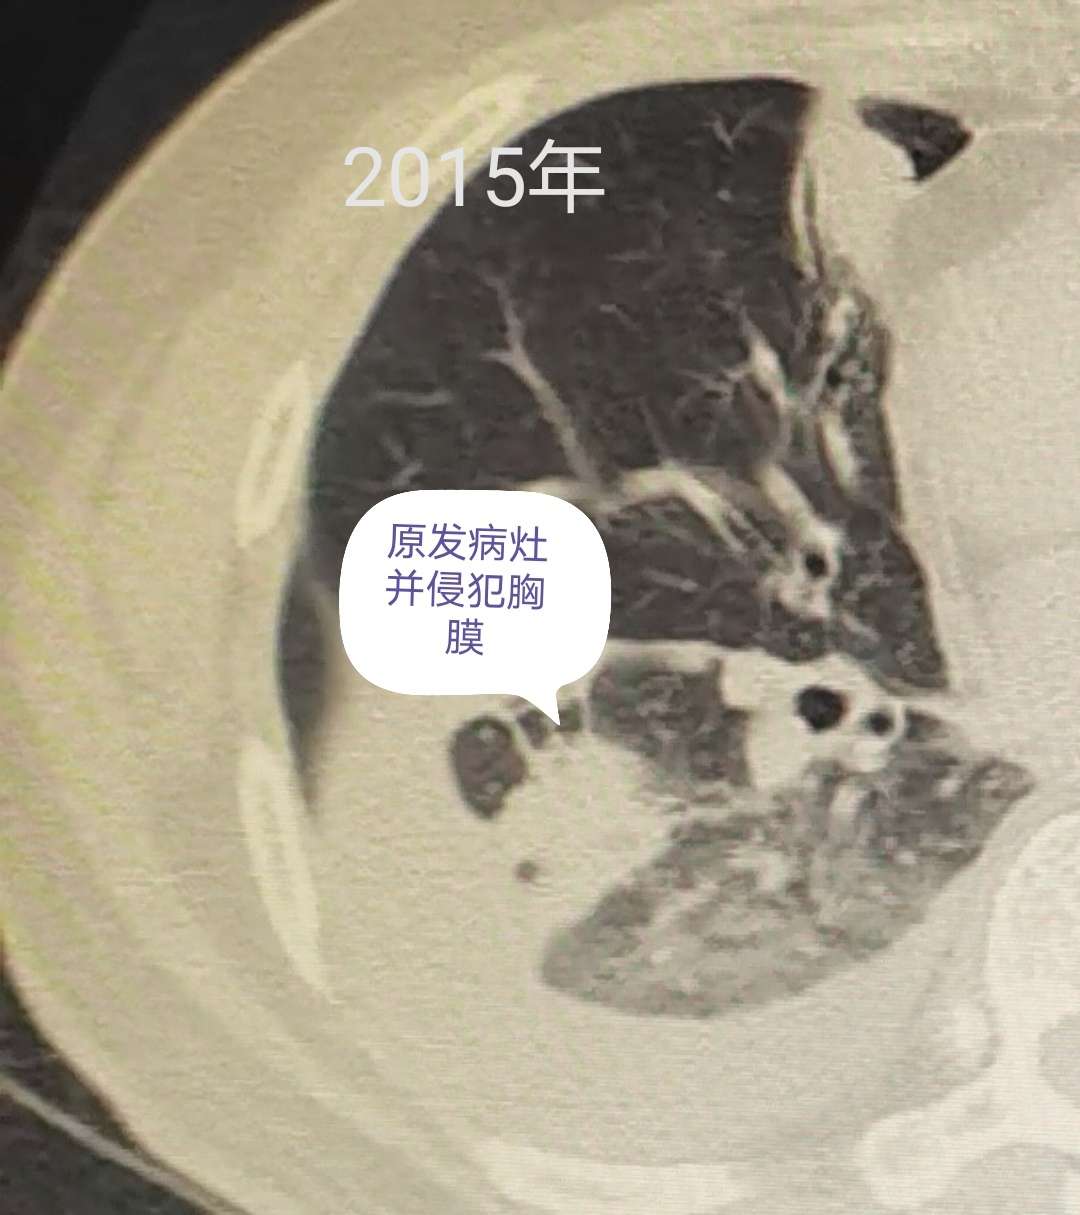

与五年前使用双免疫前的CT进行对比,这次的CT结果显示,父亲右下肺的原发病灶已经退化成一个纤维增殖灶。被累及的胸膜,已经完全恢复。胸椎骨的骨转移,也已经长好愈合。CT影像上,仅有一些慢性炎症的痕迹,已经不见癌症的踪影。

在拍这次CT之前,我家医生对父亲肺内的情况有过两种预测:第一种,就是肿瘤还在,但被免疫系统压制,进入了休眠状态;而第二种则是肿瘤已经完全被免疫系统绞杀,不复存在。由于父亲五年前已经多发远端转移(包括4处颅内转移),医生倾向于第二种可能性会更接近父亲体内的真实情况。而这次的CT结果,则证实了医生的预测是正确的:肿瘤并不是休眠,而是已经彻底被消灭。